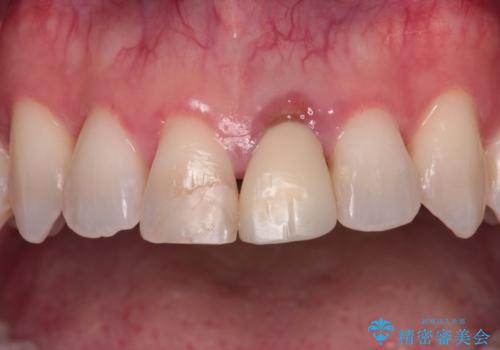

- 他院でインビザラインによる矯正治療を行っているものの、前歯の変色が気になるとのことで来院された患者様です。

インビザラインでの矯正治療がそろそろ終了とのことで、新しいインビザラインセットを発注する前に気になっている前歯2本をオールセラミッククラウンにて補綴治療を行うこととしました。

歯肉の腫脹が認められたため、仮歯へ置き換える過程で腫脹改善の指導などを行い、よりよい状態で治療を行うこととしました。